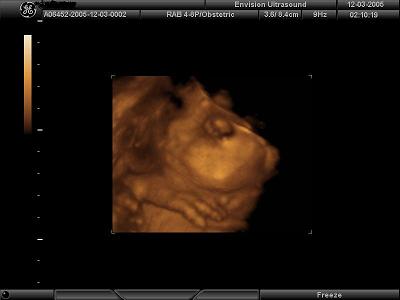

4D Ultrasound pics

We went to Envision in NJ yesterday to get our 4D ultrasound done for our 7 year wedding anniversary. It was the best gift we have ever given to each other!! Our little girl looks just like daddy but has mommys one dimple on her left cheek She is so beautiful and was playing with her umbilical cord the whole time trying to shove it in her little mouth. It was so fun to watch!! I would highly recommend getting it done. I posted my 4 fave pics out of 35 that we came home with and a lovely DVD set to music. Image Attachment(s):